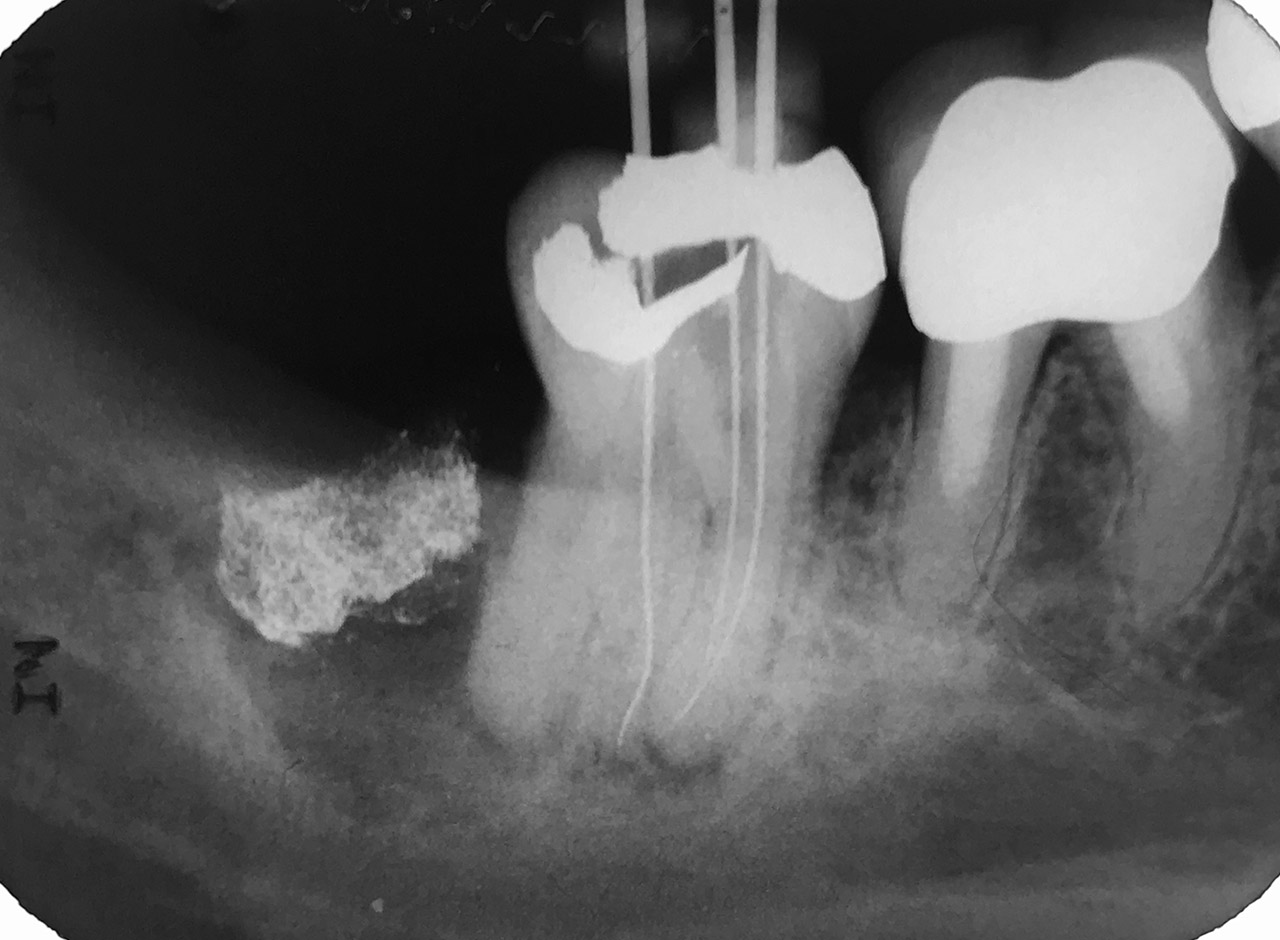

Wurzelbehandlung/Endodontie:

Massiver Paro-/Endodefekt bei den Zähnen 38&37. Extraktion von 38 (Weisheitszahn) und Wurzelbehandlung von 37 (4 Kanäle). Defekt vollständig ausgeheilt.